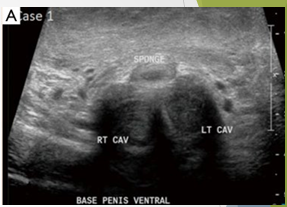

Patient attempting to urinate whilst penis erect. Heard ‘crack’ followed by acute pain

Normal anatomy at the base of the penis: Bilateral homogenous CC, Thin line of intact Tunica albuginea, Corpus spongiosm well demarcated